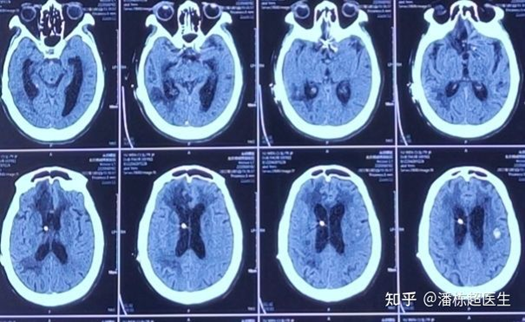

术后给与患者低压引流后,第二天就恢复了清醒!

效果:术后第二天患者清醒,遵嘱动作。